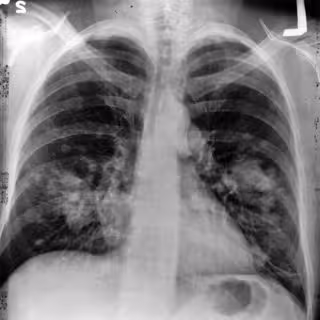

La falta de un cribado efectivo dificulta el diagnóstico precoz del cáncer de pulmón

Cada año se detectan 20.000 nuevos casos de cáncer de pulmón en España, aunque más de la mitad están ya en fase avanzada dado que "actualmente no existe ninguna prueba de cribado que permita su diagnóstico precoz".

"El 'screening' en pulmón es complejo, porque la placa de tórax diagnostica tumores de ya un centímetro y medio, y la confirmación histológica requiere pruebas adicionales como broncoscopias o biopsias para estar seguros de que lo que tenemos en frente es un carcinoma", explica López Criado.